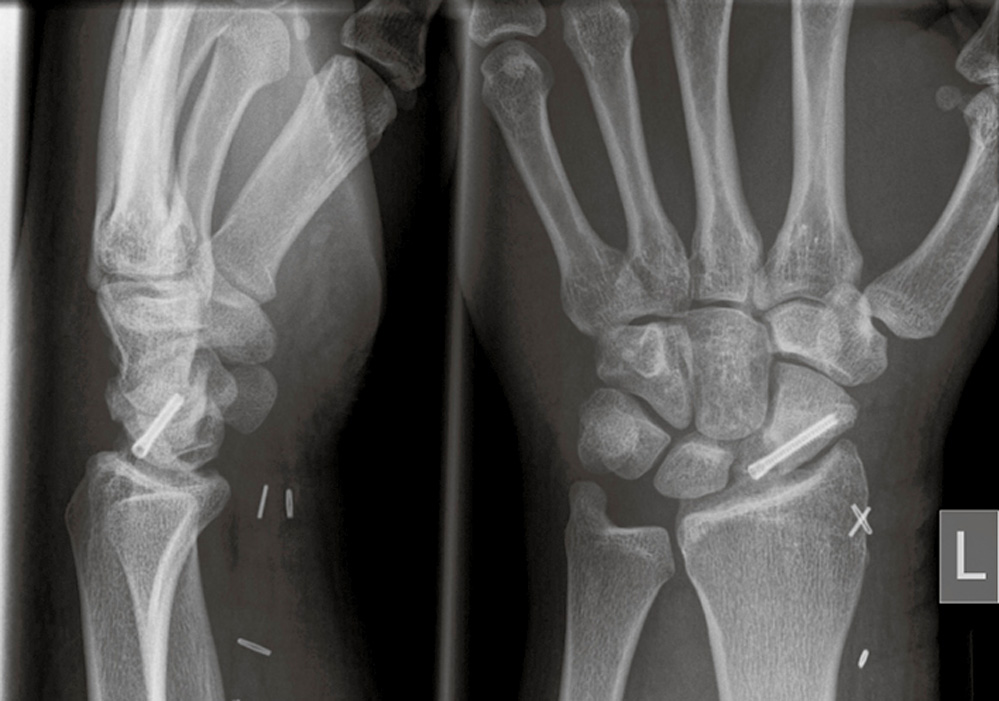

Anamnese: Ein 25-jähriger Mann hatte sich im Alter von 20 Jahren beidseits eine Kahnbeinfraktur bei einem Sturz beim Fußball zugezogen. Rechts erfolgte eine Schraubenosteosynthese, links eine konservative Behandlung. Beidseits kam es zur knöchernen Heilung. Im Alter von 24 Jahren stürzte er erneut auf das linke Handgelenk.

Diagnostik: Die in einer Klinik erfolgte Diagnostik am Unfalltag ergab keinen Frakturnachweis. Entsprechend erfolgte keine Ruhigstellung. Bei anhaltenden Beschwerden wurde gleichenorts nach einem dreiviertel Jahr eine Kernspinuntersuchung durchgeführt, die eine Fraktur des proximalen Kahnbeinpols mit Verdacht auf Minderdurchblutung des proximalen Fragmentes ergab (Abbildung 3), weshalb der Patient zugewiesen wird.

Die CT in „Superman-Position“ des Patienten (Bauchlage, Arm im Winkel von 45° zur Körperlängsachse über dem Kopf gelagert) in Dünnschichttechnik (Schichtdicke optimal 0,5 bis 0,6 mm) mit Aquirierung der Bilder in der Kahnbeinlängsachse zeigte ein extrem kleines proximales Fragment und eine ausgedehnte Zystenbildung im proximalen Kahnbeinpol (Abbildung 4 a, b).

Abbildung 4 a und b: Schräg-koronale (a) und schräg-sagittale (b) CT-Aufnahme in Richtung der Kahnbeinlängsachse: extrem kleines proximales Fragment mit ausgedehnter Zystenbildung im proximalen Kahnbeinpol.

Abbildung 6: Röntgenaufnahme des linken Handgelenks in zwei Ebenen direkt postoperativ: Die knorpeligen Anteile des Spans sind schattenhaft zu erkennen. Der Span ist zum distalen Kahnbeinanteil mittels vollständig intraossär liegender Schraube fixiert.

Für drei Monate wurde postoperativ ASS 100 mg/Tag verordnet. Die Ruhigstellung konnte zehn Wochen postoperativ mittels Röntgen- (Abbildung 7) sowie Kahnbein-CT-gesicherter weitgehender Durchbauung aufgehoben und mit der krankengymnastischen Beübung begonnen werden. Fünf Jahre postoperativ bestand Beschwerdefreiheit mit Beweglichkeit des Handgelenkes für Streckung/Beugung 60-0-50° (Abbildung 8 a bis d) bei unauffälligem radiologischen Befund.

Abbildung 7: Röntgenaufnahme des linken Handgelenks in zwei Ebenen zehn Wochen postoperativ: Einbau des osteochondralen Spans; skapholunärer Spalt etwas erweitert.